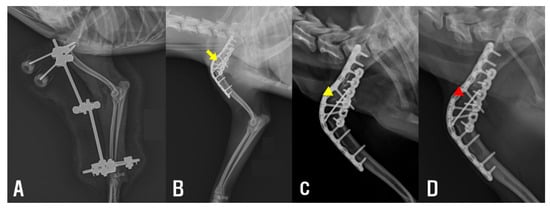

Subsequently, a lateral approach was performed to further release periarticular soft tissues. The insertion site of the extensor carpi radialis muscle was also released (Figure 2C), resulting in a measurable improvement in the elbow’s ROM, with the range of motion extending to approximately 135°. To maintain the corrected extension angle and prevent recurrence of contracture, a trans-articular ESF was applied (Figure 2D). A 35 mm circular ring (IMEX Veterinary, Longview, TX, USA) was affixed to the distal radius using two 0.9 mm Kirschner wires (K-wire, Top Medical Company, Seoul, Republic of Korea). Additionally, two 2.4 mm end-threaded pins (Duraface ESF, IMEX Veterinary) were placed in the humerus and secured using lateral connecting rods. Postoperatively, the patient received cefazolin (22 mg/kg, intravenously) for seven days until negative culture results were confirmed. Remifentanil (0.1 μg/kg/min, constant rate infusion) was tapered over two days. Meloxicam was administered (0.2 mg/kg, subcutaneously) on day 1, followed by oral administration (0.1 mg/kg) once daily for an additional 6 days. The patient was discharged one week after surgery and continued with outpatient management consisting of wound care. The fixator was maintained for two weeks (Figure 3A). Passive ROM exercises were initiated immediately following fixator removal to promote soft tissue flexibility and to reduce the risk of recurrence. These exercises were performed three times daily on both the elbow and carpus within a pain-free range of motion. Gradual improvement in elbow extension was observed over the following weeks. The frequency of intermittent non-weight-bearing episodes appeared to decrease over time, based on subjective owner observation and clinical examination. Prior to shoulder arthrodesis, elbow ROM measurements demonstrated substantial recovery, with the right elbow showing flexion of 20° and extension of 148°, and the left elbow showing flexion of 22° and extension of 142°.

Figure 3. (A) Immediately after elbow muscle release, showing improved elbow extension and joint alignment. (B) Immediately after shoulder arthrodesis, demonstrating appropriate implant placement. A gap is observed at the arthrodesis site (yellow arrow). (C) One month postoperatively after shoulder arthrodesis, showing a reduction of the gap at the arthrodesis site compared with the immediate postoperative image (yellow arrowhead). (D) Four months postoperatively after shoulder arthrodesis, showing near-complete disappearance of the gap at the arthrodesis (red arrowhead).